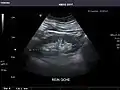

Left kidney

Kidneys: Right and left kidneys measure 11.5 cm and 12 cm in length respectively. No hydronephrosis. Small left lower pole kidney cyst.